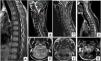

Presentamos el caso de un varón de 17 años que acude a urgencias por cervicalgia de 6 semanas de evolución, sin déficit neurológico. La tomografía y resonancia magnética mostraban una masa dependiente de C2 con infiltración de partes blandas e invasión del canal medular, sin signos de mielopatía. Se realizó biopsia guiada con tomografía. Esperando al resultado, el paciente desarrolló una tetraparesia aguda con incompetencia de esfínteres. Una nueva resonancia magnética mostró un aumento de la masa ósea tumoral con extensión epidural, mielopatía y nuevas lesiones vertebrales. Se realizó una resección posterior y descompresión medular de urgencia, con fijación occipito-cervical. La recuperación postoperatoria fue completa. La inmunohistoquímica reveló un sarcoma de Ewing. Se inició quimioterapia con respuesta parcial. El sarcoma de Ewing primario atlantoaxial es una entidad excepcional con mal pronóstico. Su tratamiento es multidisciplinar, incluyendo una resección total si es posible, lo cual supone un reto para el cirujano.

We report the case of a 17-year-old male presented to the emergency department with a six weeks history of neck pain and no neurogical deficit. Computed tomography and magnetic resonance imaging revealed an expansile lesion in the axis, with soft tissue and spinal cavity invasion, without mielopathy signs. Tomography-guided mass biopsy was taken. Waiting for histopathologic results, the pacient developed acute tetraparesis and sphincter incompetence. Magnetic resonance revealed that the bone mass had grown with epidural compromise, mielopathy and new vertebral lesions. Medular decompression with laminectomy, excision of the posterior elements of axis with the involved soft tissue mass and occipito-cervical fixation was performed. Neurological recovery was complete. Inmunochemistry revealed an Ewing Sarcoma. Chemoteraphy treatment was given, with partial response. Primary Ewing sarcoma of atlas-axis is a rare entity with poor prognosis. Multidisciplinary approach treatment is needed, with a total surgical resection if it is possible, a real challenge for the surgeon.